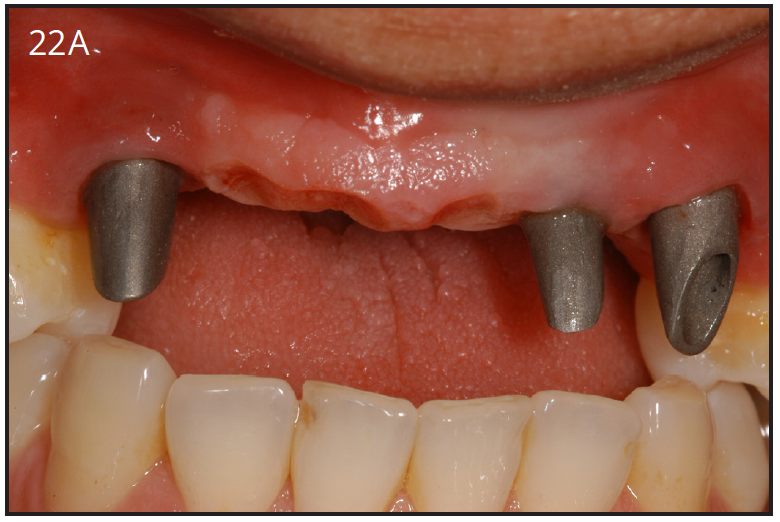

There are different types, shapes and sizes of abutments that are either pre-fabricated by the manufacturer, or they are custom made by the dental lab. (Figure 22A) The choice of abutment is made by the esthetics desires, thickness of tissue around the implant, and the angle of the implant. What is important to remember is that all abutments are connected to the implant using a screw.

Figure 22A – Titanium custom abutments

Figure 22